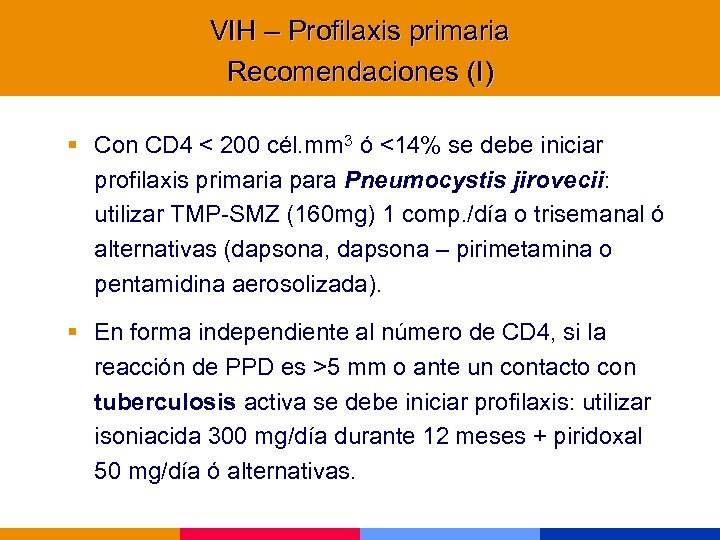

VIH – Profilaxis primaria Recomendaciones (I) § Con CD 4 < 200 cél. mm 3 ó <14% se debe iniciar profilaxis primaria para Pneumocystis jirovecii: utilizar TMP-SMZ (160 mg) 1 comp. /día o trisemanal ó alternativas (dapsona, dapsona – pirimetamina o pentamidina aerosolizada). § En forma independiente al número de CD 4, si la reacción de PPD es >5 mm o ante un contacto con tuberculosis activa se debe iniciar profilaxis: utilizar isoniacida 300 mg/día durante 12 meses + piridoxal 50 mg/día ó alternativas.

VIH – Profilaxis primaria Recomendaciones (I) § Con CD 4 < 200 cél. mm 3 ó <14% se debe iniciar profilaxis primaria para Pneumocystis jirovecii: utilizar TMP-SMZ (160 mg) 1 comp. /día o trisemanal ó alternativas (dapsona, dapsona – pirimetamina o pentamidina aerosolizada). § En forma independiente al número de CD 4, si la reacción de PPD es >5 mm o ante un contacto con tuberculosis activa se debe iniciar profilaxis: utilizar isoniacida 300 mg/día durante 12 meses + piridoxal 50 mg/día ó alternativas.